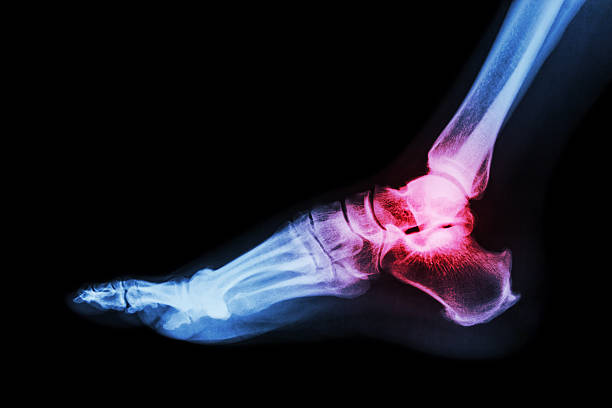

발목 관절염이란?

발목 관절염은 발목 관절 중 쿠션 역할을 하는 연골이 손상되어 염증이 발생하고, 이로 인해 발목이 붓고 통증이 생기는 질환입니다.

발목관절염의 진단

2. X-ray: 관절 간격의 감소, 골극 형성, 변형 등을 확인합니다.